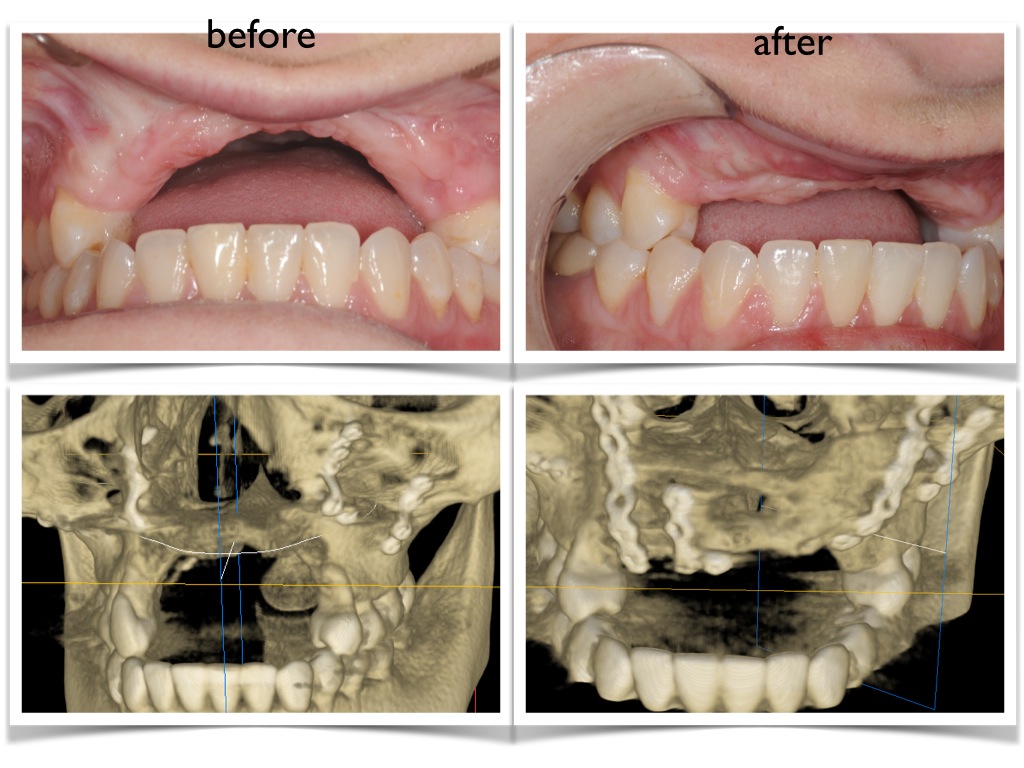

moran before and after.001 Published November 2, 2015 at 1024 × 768 in moran before and after.001 ← Previous Next →